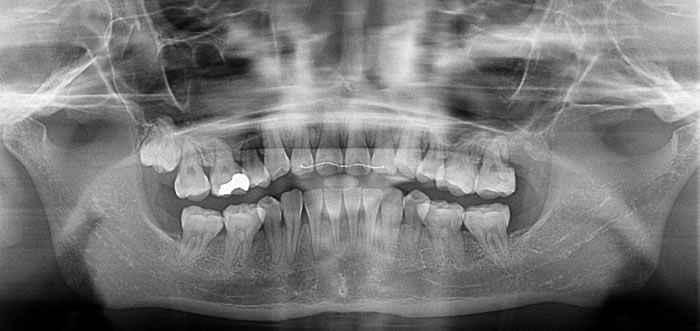

初診時のオルソパノラマレントゲン